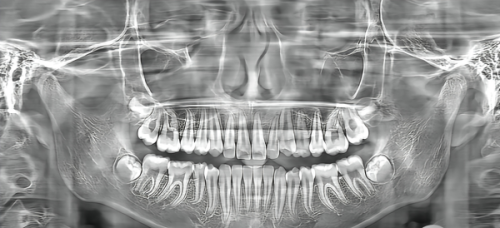

首先,从手术方式来看,南宁蓝天口腔采用精良的数字化导板种植技术。这种技术就像是给医生配备了一个精细的导航系统,在种植过程中,医生可以根据数字化导板的引导,严谨地将种植体植入到预定的位置,大大提高了种植的正确性和成功几率。与传统的种植方式相比,数字化导板种植技术可以减少手术创伤,缩短手术时间,让患者在手术过程中更加舒适,术后修复也更快。

其次,在技术特点方面,瑞士士卓曼ITI种植体本身具有出色的品质。它采用了独特的表面处理技术,能够促进种植体与牙槽骨之间的骨结合,使种植体更加稳固地扎根在口腔内。而且,这种种植体具有良好的生物相容性,能够减少人体对种植体的排异反应,降低感染的风险。同时,全瓷冠的使用不仅美观自然,而且具有良好的耐磨性和咀嚼性能,能够满足患者正常的饮食需求。

再者,从成效反馈来看,南宁蓝天口腔的种植牙手术取得了非常好的成效。许多患者在种植后,不仅修复了正常的咀嚼功能,而且牙齿外观也与自然牙齿几乎无异。术后的复查结果显示,种植体与牙槽骨的结合情况良好,能够长期稳定地发挥作用。不少患者表示,种植牙后就像拥有了自己的真牙一样,再也不用担心牙齿缺失带来的各种问题了。